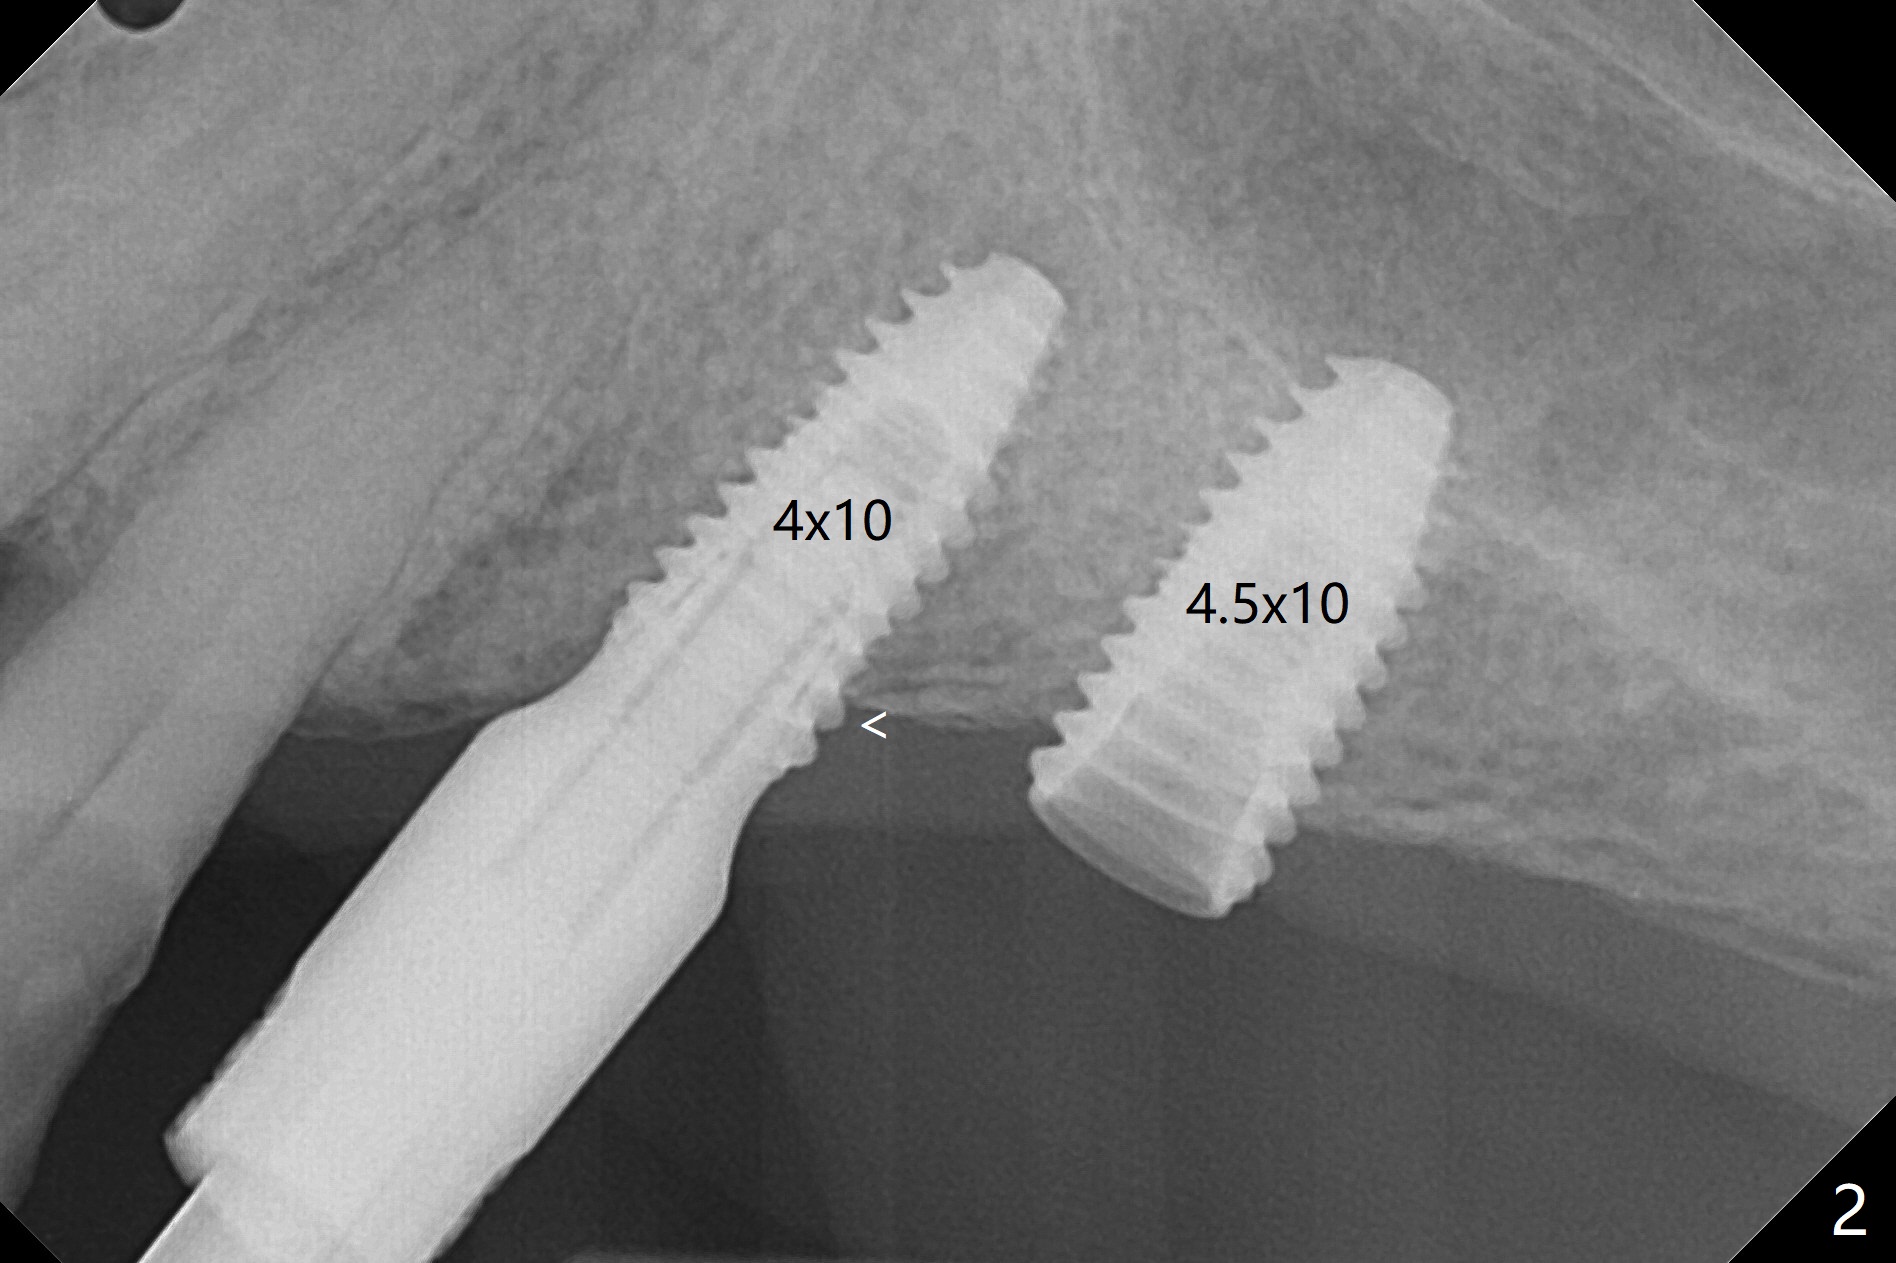

PA is taken after 2.2 mm drill reaches the depth at #13 to confirm that the osteotomy is parallel to the long axis of the tooth #12 (Fig.1). Fixture mount is used to place a 4x10 mm implant at #13 and stays as an anchor pin while osteotomy and sinus lift are being conducted at #14 (Fig.2). In fact there is discrepancy in depth using the guide. For example the last drill for osteotomy is 4.5x7.3 mm according to design, whereas 4.5x11.5 mm drill has to be used before the sinus floor has small area of perforation without sinus membrane breakage. Autogenous bone harvested from the osteotomy, PRF membrane and a 4.5x10 mm dummy implant are used for sinus lift (Fig.2). The placement depth of the implant at #13 has to be adjusted multiple times until satisfaction (Fig.2-5). The implant at #14 is infected and loosened 1.5 months postop; after its removal, the sinus floor is absent without membrane perforation; the large defect with basically intact buccal and palatal walls is grafted (Fig.6 *). Four to five months later, use the same guide and drill sequence until 3.5x7.3 mm drill. Insert a 4x10 mm dummy implant to the 2nd line of 12 mm offset and take 5x5 cm CT to determine the diameter and depth of a final implant. Use healing screw. The pattern of bone graft changes 3 months postop (Fig.7, as compared to Fig.6). Return to Upper Arch Immediate Implant, Trajectory II 矫正,糖尿病,种植水平 Xin Wei, DDS, PhD, MS 1st edition 08/06/2019, last revision 12/06/2020